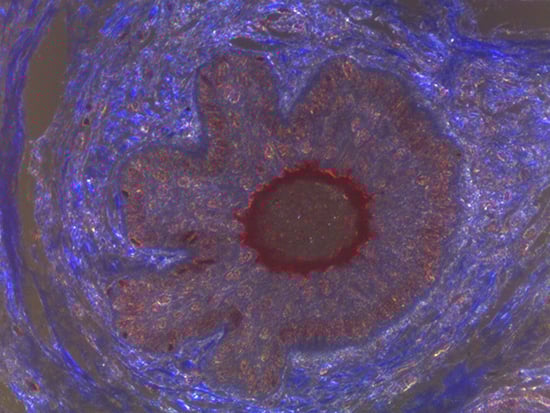

Figure 1: Brightfield Image of Dermal Tissue

Figure 2: Darkfield Imaging of Dermal Tissue

When comparing Figures 1 and 2, the visual differences are significant. A brightfield image is formed with the illumination source below the sample, and then transmitted light propagates through the sample to the sensor forming a bright, white background with sharp color. A darkfield image is formed by directing light at an oblique angle through the sample, forming a hollow cone of light which is collected by the objective. Darkfield illumination typically yields a dark background with sharp color, but in the case of Figure 2, the collagen and muscle fibers interfered with the light path and caused a blur of light and color. The dark background is hardly evident and only two distinct colors are visible. When analyzing histological stains, brightfield illumination is the preferred technique for lighting a sample.